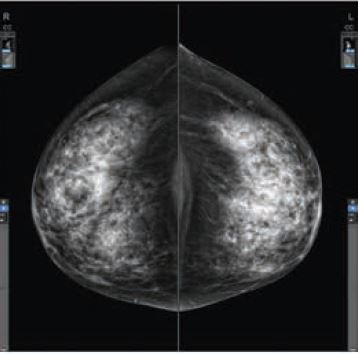

L’angiomammographie est une mammographie numérique à double énergie combinée à une injection de produit de cont...